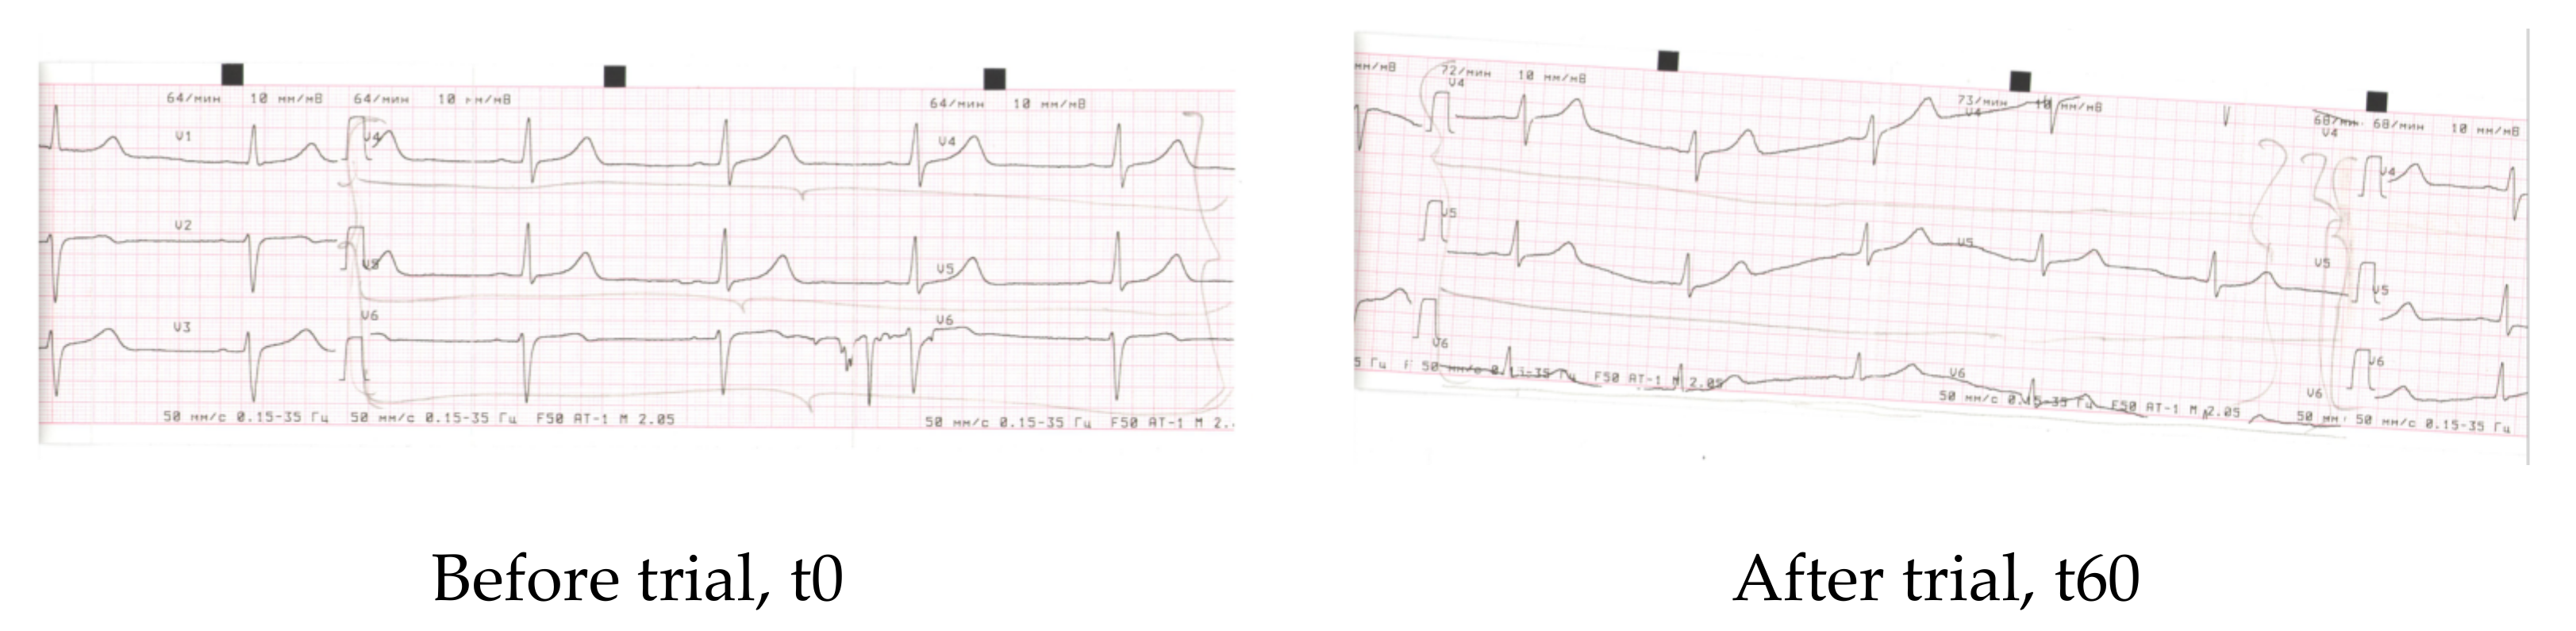

Electrocardiography measurements were carried out in the beginning (t0) and after the cessation of the trial (t60). The results were analysed by a cardiologist, and their physiological/pathological meanings were described in detail.

Electrocardiography was recorded and described by an experienced doctor-cardiologist in the beginning and at the cessation of the clinical study (scans of electrocardiography records are collected in the Appendix C. (Scan A1, Scan A2, Scan A3, and Scan A4). The doctor found that, before entering the trial, a major part of the volunteers (n = 41) did not show any abnormalities in the cardiography parameters. However, four people from the CTR group and five people from the EXP group exhibited initial stages of metabolic abnormalities in cardiac muscles, as revealed by characteristic changes in the electrocardiography peaks (V4–V6). When analysed for the second time, none of the volunteers of the EXP group showed negative metabolic changes of electrocardiography curves (Appendix C. ScansA1–A3). At the same time, all four participants of the CTR group with metabolic abnormalities retained the same after the trial (Appendix C. Scan A4).

Obviously, the human cohort was too small to come to definite conclusions that HIDW consumption for at least 2 months could alleviate potentially dangerous baseline metabolic alterations in the myocardium. However, keeping in mind that the improvement of cardiac metabolism corresponded to improved heart functions, HIDW consumption under the conditions of this study could result in a markedly faster recovery and in a better physiological state after moderate physical load (Table 5 and Table 6).

The improvement of cardiovascular system metabolism and function upon consumption of HIDW by animals has been previously shown [34]. This corresponds to our observations in the human cohort (Appendix C) and could be at least partly explained by the increase in ATP levels available for cardiac muscle contraction-relaxation, by an improvement of energy-producing metabolism and by a water loss through enhanced urination or sweating. Of course, these limited data of electrocardiography should be considered as preliminary observations. Larger studies may confirm or reject them; therefore, they are not included in the study conclusions.

Appendix C

Electrocardiography scans and their description.

Scan 1. EXP group, patient K., F, 32 y.

| Parameter | Before | After 60 days |

| Rhyme | Synus | Synus |

| Heart rate | 52 | 69 |

| PQ | 0.22″ | 0.15″ |

| QRS | 0.1″ | 0.1″ |

| QT | 0.41″ | 0.40″ |

| QRS axis | Vertical +88 | Vertical +88 |

| Conclusions | Bradicardia, dysmetabolic alterations of myocardium (frontal and lateral walls of the left ventricle) (V4–V6) | Normal rhyme, improvement of re-polarisation (V4–V6) |

Scan 2. EXP group, patient M., F, 35 y.

| Heart rate | 68 | 70 |

| PQ | 0.12″ | 0.14″ |

| QRS | 0.08″ | 0.08″ |

| QT | 0.38″ | 0.38″ |

| QRS axis | Vertical +77 | Vertical +77 |

| Conclusions | Dysmetabolic alterations of myocardium (frontal and lateral walls of the left ventricle) (V4–V6) | Improvement of re-polarisation along frontal and lateral walls of the left ventricle (V4–V6) |